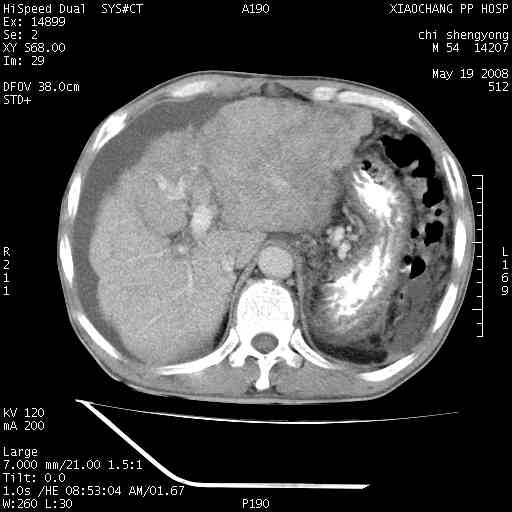

以下是引用zjzjr在2008-5-21 10:52:00的发言:[br]肝左叶巨块型肝癌伴门静脉左支瘤栓形成.肝硬化、腹水,胃底静脉曲张,脾术后改变。

以下是引用随光逐影在2008-5-21 16:20:00的发言:[br]1)肝左叶肝癌伴门静脉左支瘤栓形成,腹膜后淋巴结转移。2)肝硬化、腹水、胃底静脉曲张。3)胆囊炎。4)脾脏缺如,为切除术后所致。